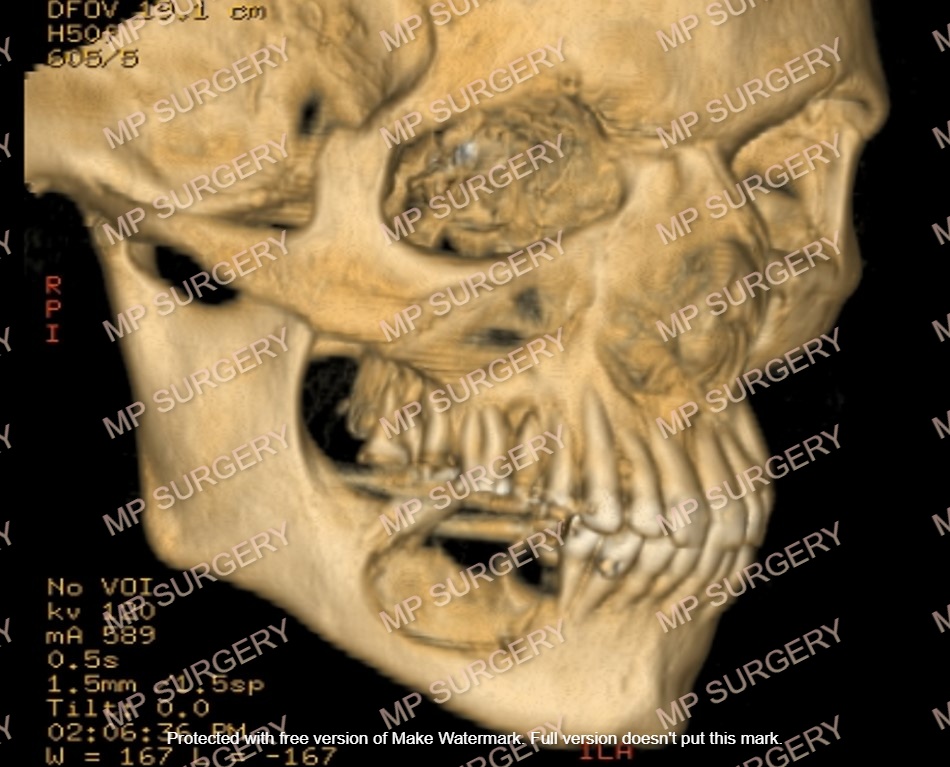

Οι κύστεις των γνάθων μπορεί να αυξηθούν πολύ σε μέγεθος πριν δώσουν συμπτώματα όπως πόνο και πρήξιμο. Επίσης μπορεί να επεκταθούν σε σημαντικές ανατομικές δομές των γνάθων όπως το ιγμόρειο άντρο στην άνω γνάθο, τη ρινική κοιλότητα και το κάτω φατνιακό πόρο.

Σε κάθε περίπτωση οι κύστεις αυτές πρέπει να αφαιρούνται.